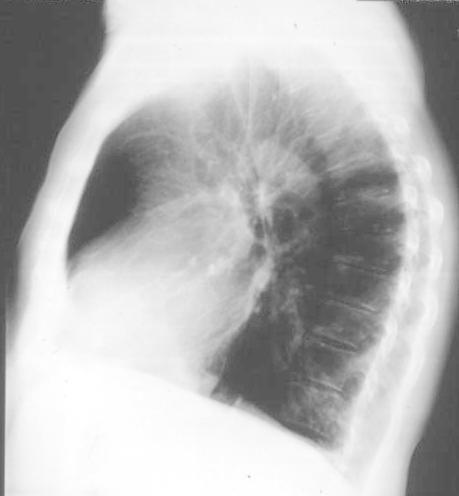

The

Lateral Films

1. Lung

Fields in front and behind the heart

= Same Density

2. Density over the heart

= density over upper thoracic spine

|

3. Check

the position of FISSURES

4. The Hila (density, size, etc)

5. Vertebral bodies